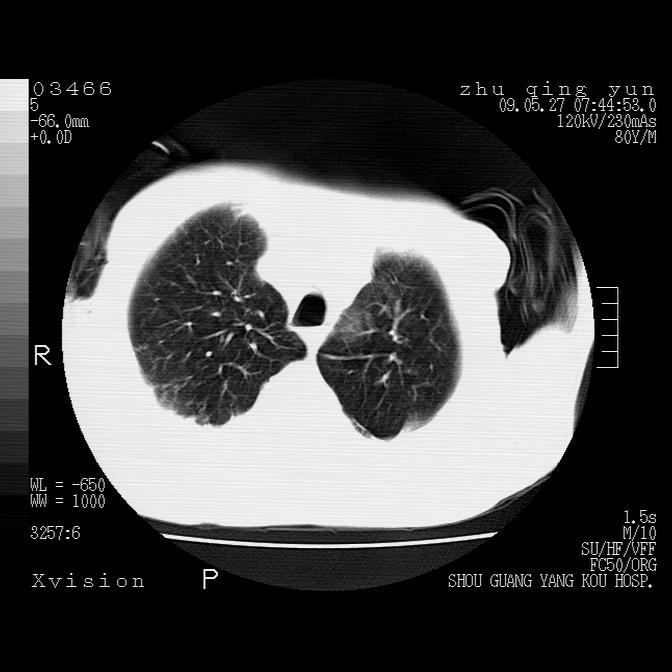

病人男性,年龄80,气喘来院,其他病史不太详细,1月前有过恶心,呕吐,在当地人民医院做过钡餐,诊断胃炎,

1)考虑左肺中央型肺癌并阻塞性肺炎,后下纵隔受侵伴纵隔淋巴结转移。2)双侧少量胸腔积液,胸膜增厚。3)心包积液。

左肺下叶见多发片状及结节状病灶,左肺基底段支气管闭塞,纵隔内见多发淋巴结肿大,纵隔向左侧移位,左侧胸廓变小。应该是左肺下叶中心型肺癌,纵隔淋巴结转移,左侧肺内转移,左肺基底段肺不张,阻塞性肺炎。

1)考虑左肺中央型肺癌并左肺下叶阻塞性肺炎、不张;左胸膜腔积液、心包积液、纵隔淋巴结转移;癌肿累及左心房。2)左心室大。冠状动脉壁钙化斑。